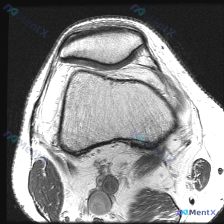

大家好,今天分享一个非常有临床意义的读片病例,核心矛盾点很值得讨论。 病例基本信息 本病例提供了膝关节MRI T1序列轴位髌股关节层面影像,临床提示存在软骨异常,要求读片分析。 影像学所见 本次扫描层面为髌股关节层面,影像可见: 1. 髌骨、股骨髁关节软骨:髌骨后方软骨连续光滑,股骨滑车软骨厚度均匀...

刚遇到一份有意思的膝关节影像病例,整理出来和大家分享一下思路。 病例基本信息 这是一份膝关节MRI T1序列轴位单张图像,核心疑问是评估是否存在「软骨异常」。 影像读片结果 1. 扫描层面是膝关节上部,主要显示髌股关节(髌骨+股骨滑车)和股骨髁 2. 髌骨软骨下骨、股骨髁骨皮质轮廓清晰,骨松质信号均...